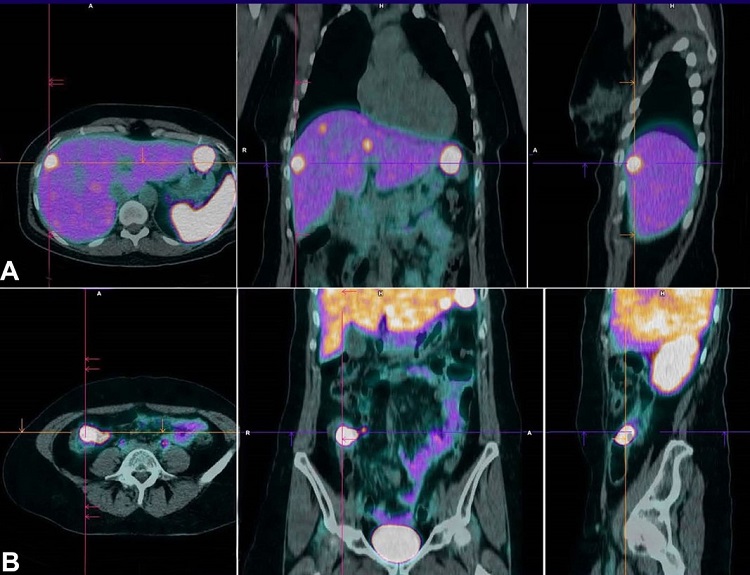

A PET 68Ga-DOTANOC was performed to determine the location of the primary neuroendocrine tumor as well as the extension of the disease, and it was conclusive for liver metastases and a primary tumor in the ileocecal topography with high expression of somatostatin receptors (Figure 6).